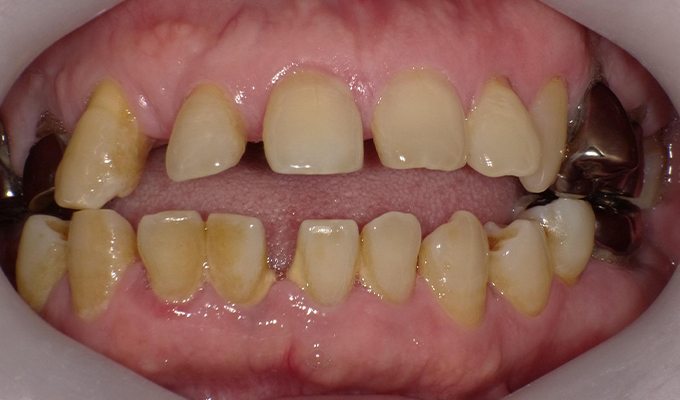

初診時(2010年)

初回メンテナンス時(2012年)

- 40代女性 (2010年)

- 5年ほど前に上に総入れ歯を作った。(マグネットタイプ)食事してたら人口歯が取れてしまった。インプラントに興味がある。40代なので入れ歯はやっぱり嫌、とのことでした。

- 治療内容

- 上・・・虫歯の根だけの歯が数本残っているためすべて抜歯し仮義歯作成しました。最終的には8本インプラントを埋入し上部構造はメタルボンドです。

下・・・保存できる下の歯はメタルボンドブリッジにし、奥歯のない部分に3本インプラントを埋入しました。治療期間は2年ほどかかりましたがしっかり食事ができるようになったので嬉しいと、満足していただけました。

以降定期的にメンテナンスに来院いただき11年経過してもいい状態を維持されています。